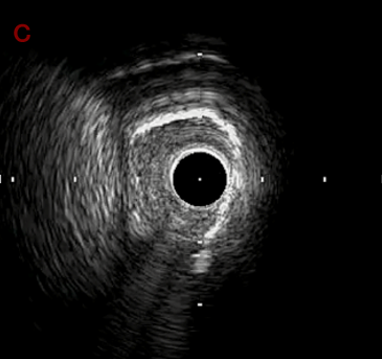

IVUS after OAS low speed 3回

IVUS imaging after low speed 3回

OAS low speedによる引きのsandingを3回行いIVUSを確認するとa-cでは心筋側側へのOASによる良好なbias変化と、それに伴いdの健常側への危険なbias変化を認めた。

そのためcでIVUSマーキングを行い、その点より引きで赤線のpinpoint OAS high speedを行い、dに関してはinjury回避のためにOASを当てない方針とした。